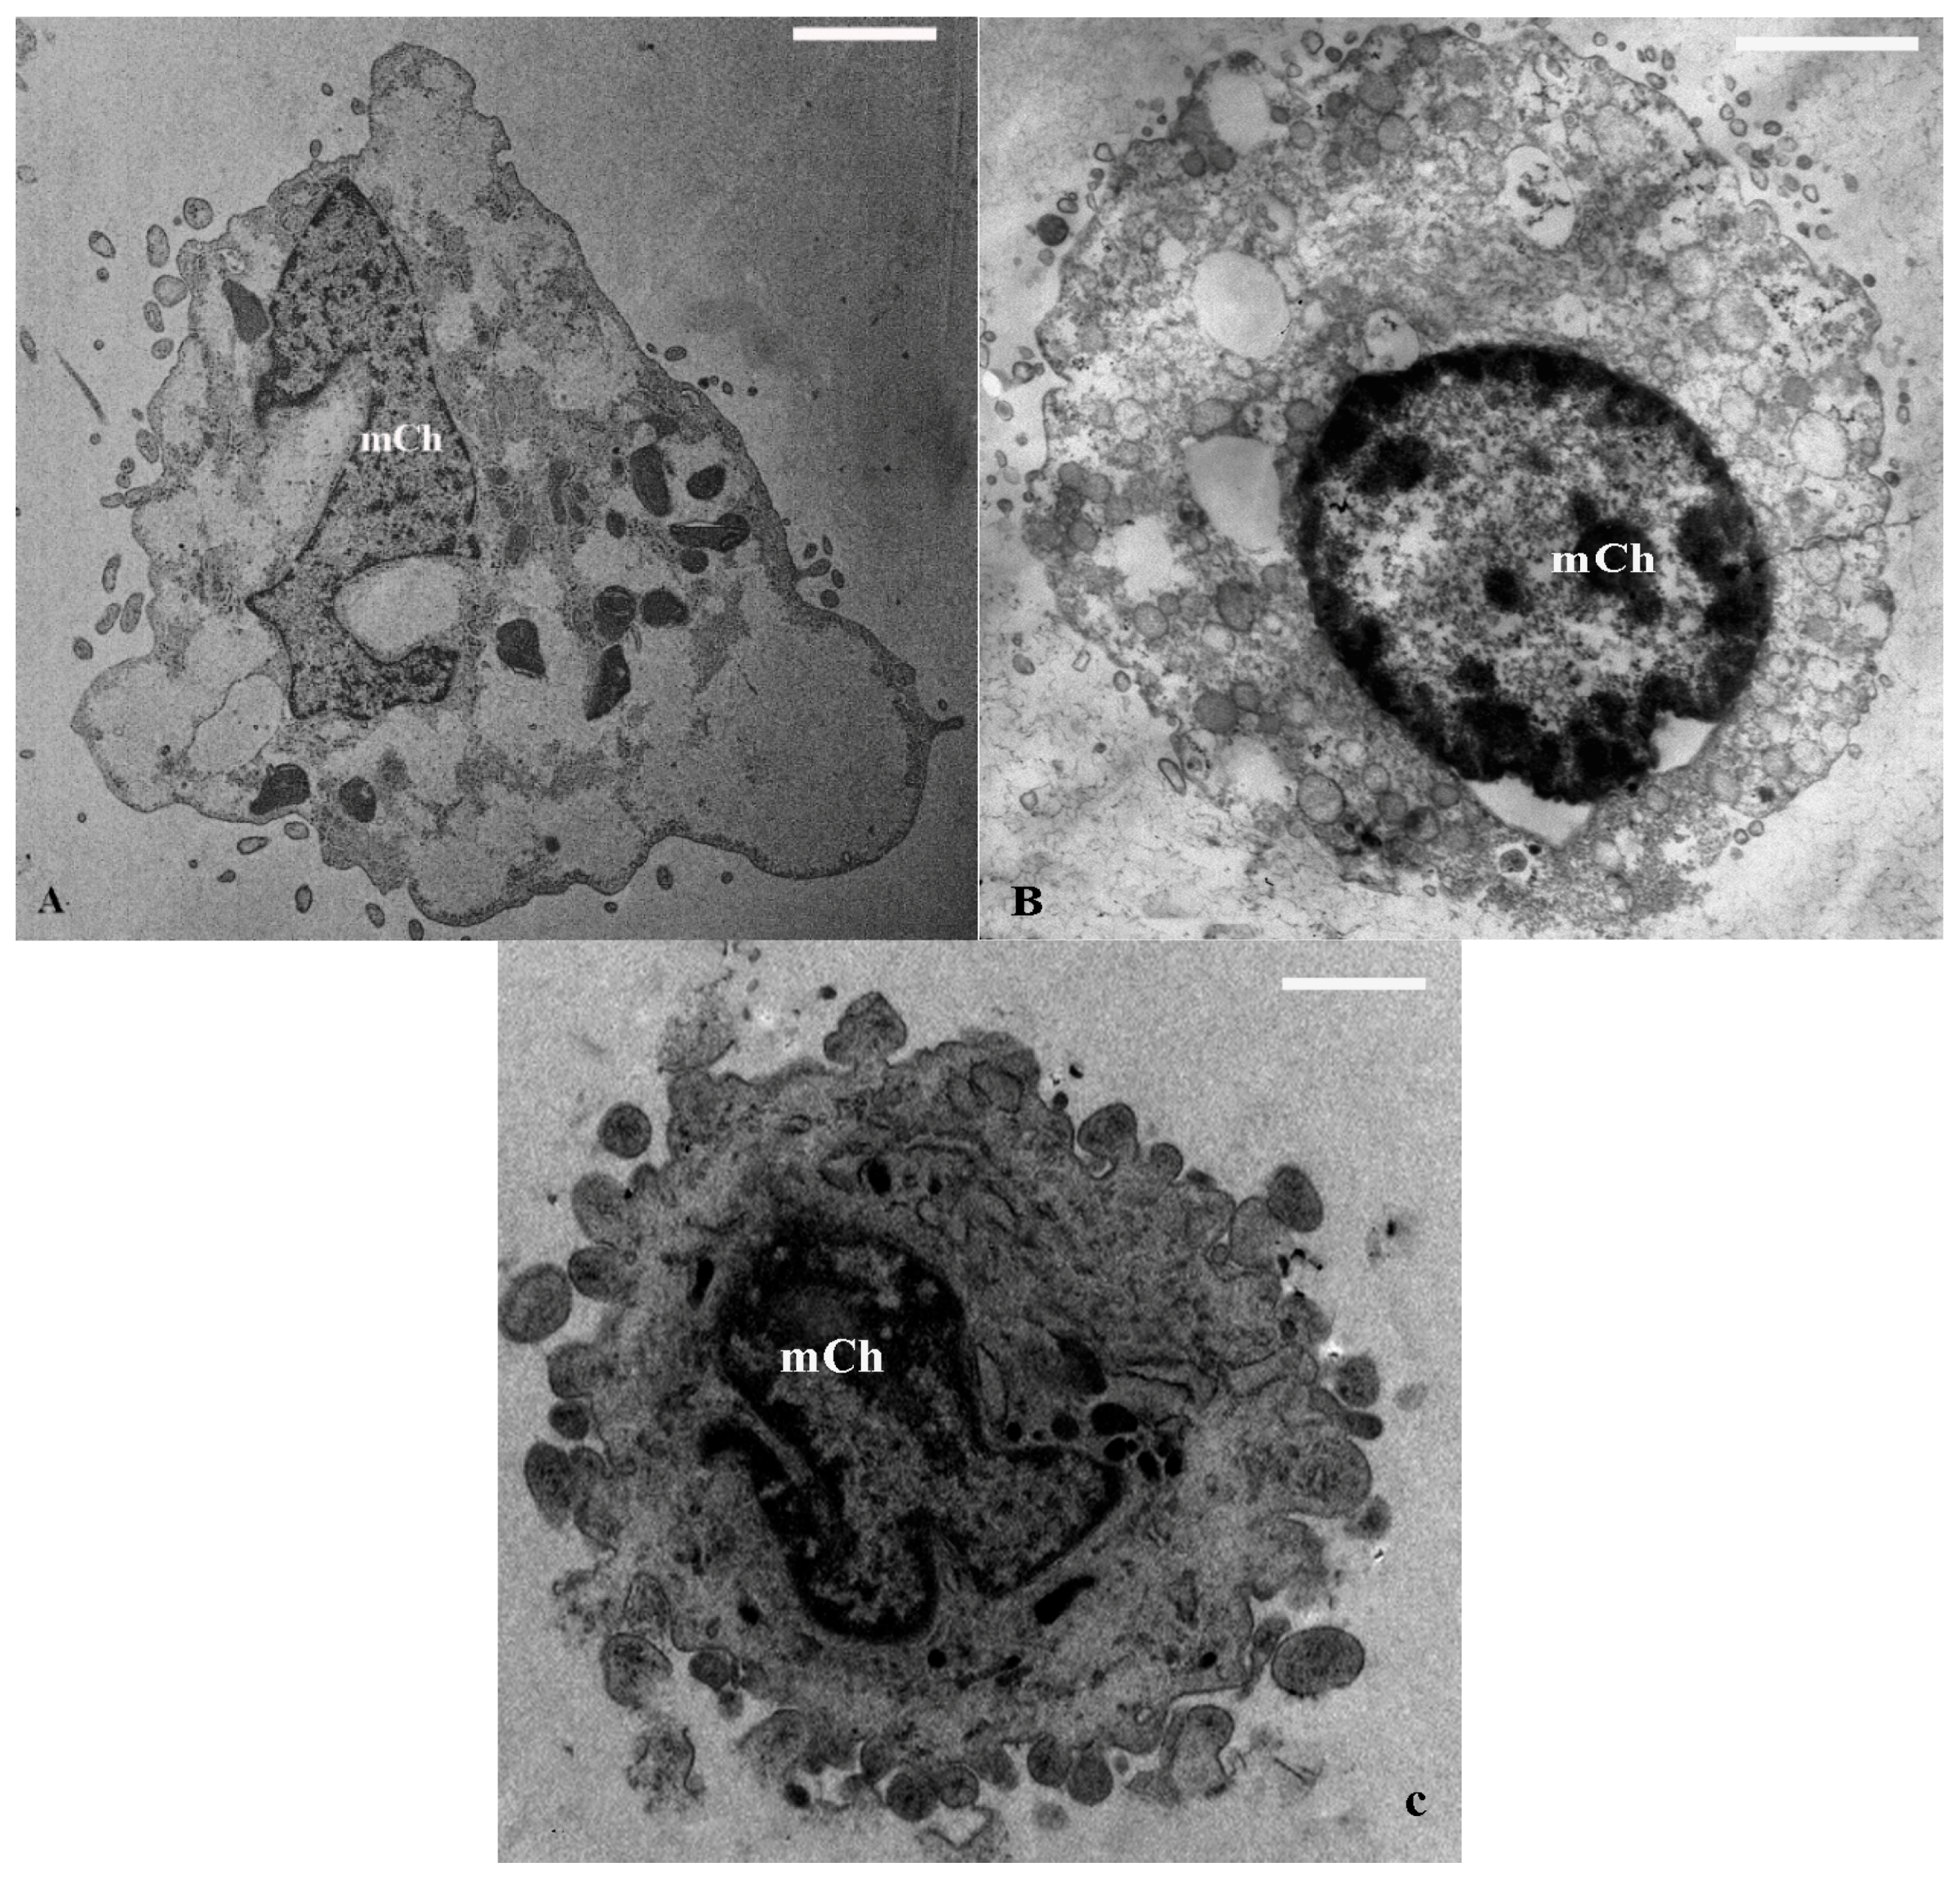

2.1. TEM and SEM Analysis

| Marginated Chromatin (cells %) | 5 ± 2.1 | 12 ± 1.7 ** | 10 ± 2.4 | 30 ± 2.7 ** | 5 ± 2.5 | 10 ± 1.9 | 7 ± 2.2 | 18 ± 1.8 * |